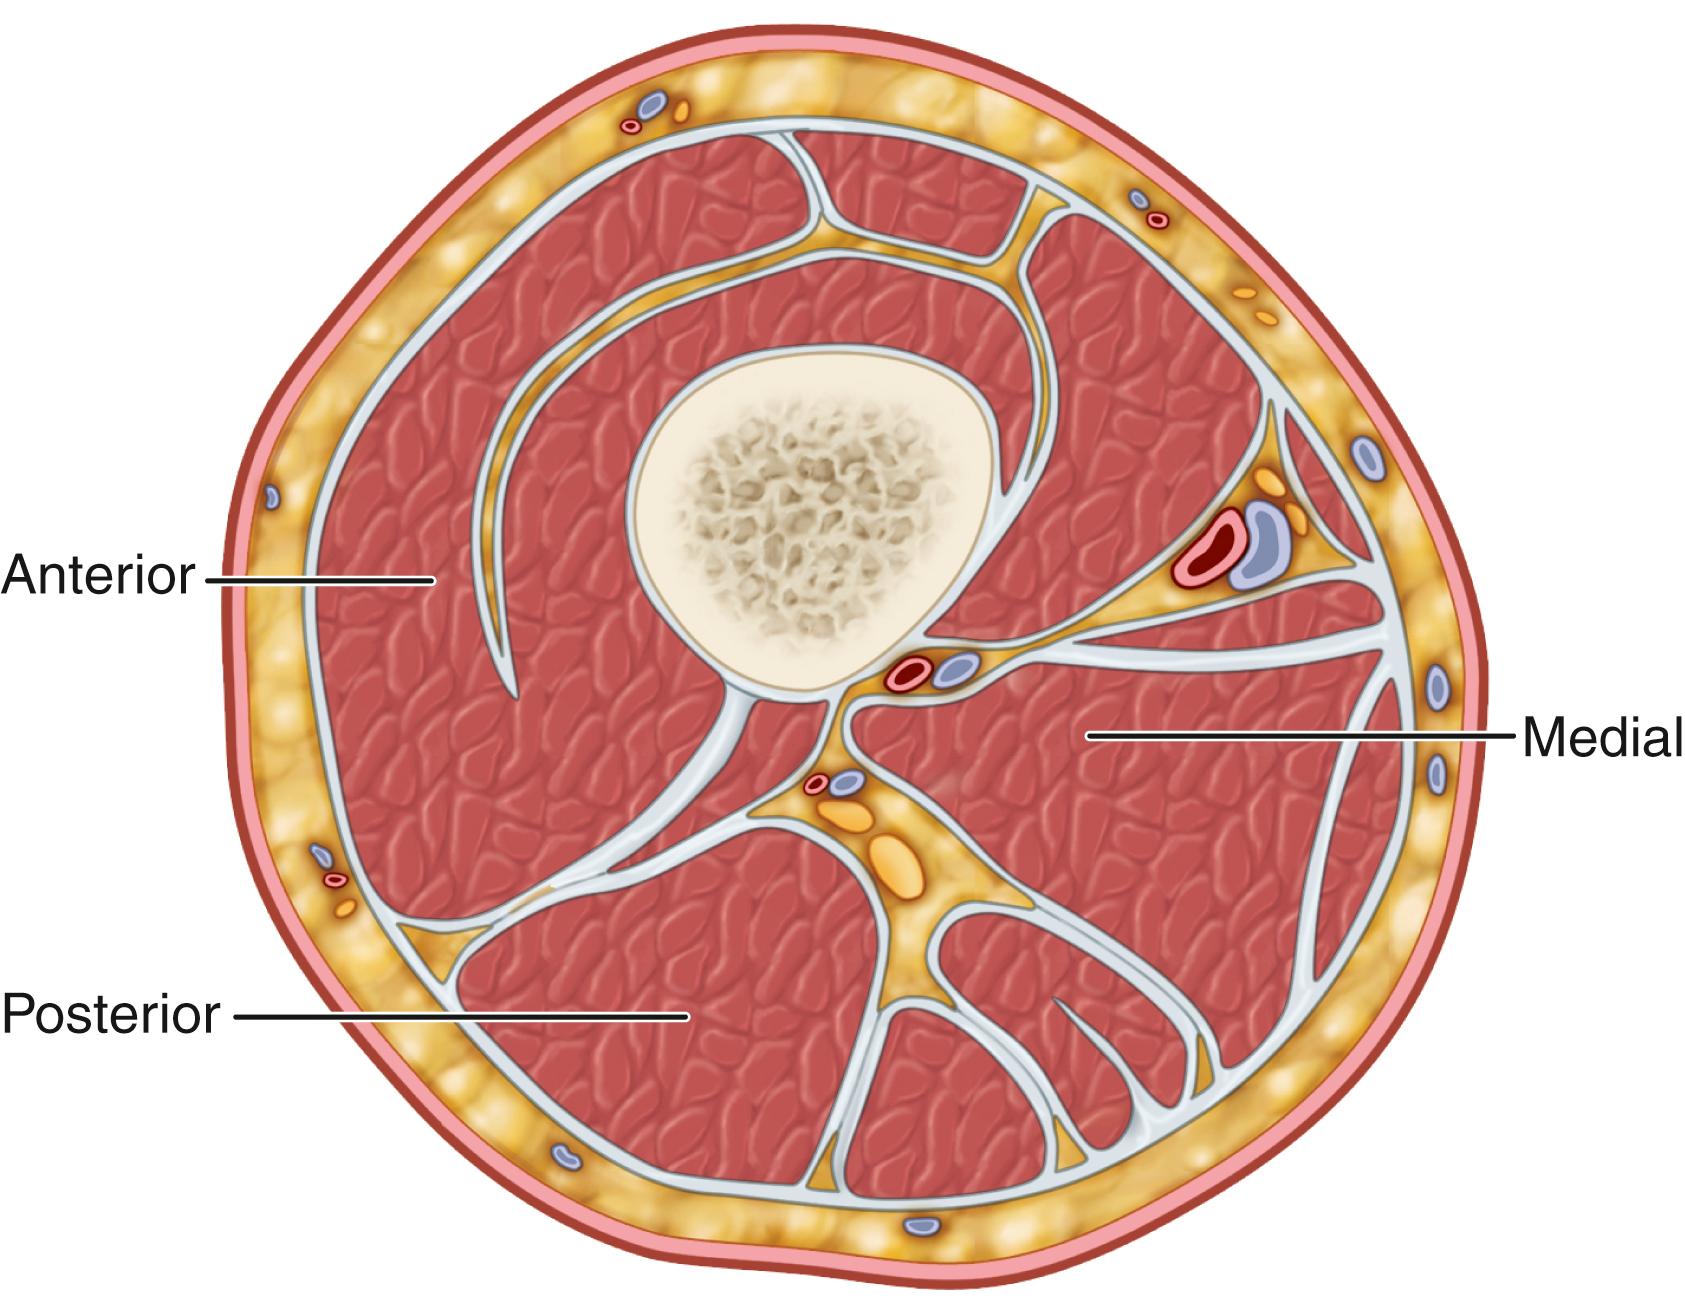

Compartment syndrome is an elevation of the interstitial pressure in a closed osteofascial compartment that results in microvascular compromise. Compartments with relatively noncompliant fascial or osseous structures most commonly are involved, especially the anterior and deep posterior compartments of the leg ( Fig. 48.1 ) and the volar compartment of the forearm. Compartment syndrome can develop anywhere skeletal muscle is surrounded by substantial fascia, however, such as in the buttock, thigh, shoulder, hand, foot, arm, and lumbar paraspinous muscles.

FIGURE 48.1, Four compartments of leg: transverse section through middle portion of left leg.

The myofascial compartments of the thigh have a considerably larger volume and potential capacity than those of the lower leg or forearm, accounting for the relative infrequency of thigh compartment syndrome. The thigh is divided into three distinct compartments (anterior, medial, and posterior) by intermuscular fascial extensions ( Fig. 48.5 ); collectively, the compartments are encased by the fascia lata. Within the anterior compartment are the quadriceps muscle group and the sartorius muscle, the femoral nerve and its sensory branch, the saphenous nerve, and the femoral artery and vein. The medial compartment contains the adductor muscle group and its neurovascular supply, the profunda femoris and obturator arteries, and the obturator nerve. In the posterior compartment are the biceps femoris, semimembranosus and semitendinosus muscles, arterial branches of the profunda femoris, and the sciatic nerve. Most reported compartment syndromes of the thigh involve the anterior compartment because it is surrounded by the stiffest walls laterally and medially (fascia lata and iliotibial tract) and is the most vulnerable to trauma.